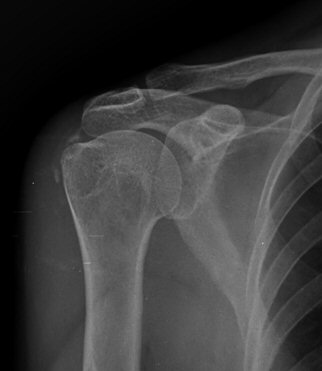

´Ü¼ø¹æ»ç¼±°Ë»ç

¼®È¸È­ À½¿µÀÌ °üÂû µÊ(±×¸² 9, 10)